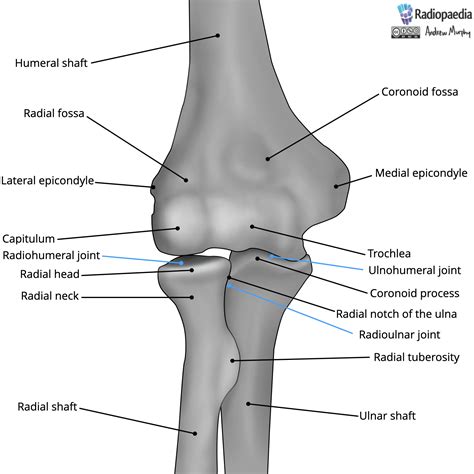

The olecranon is the bony prominence at the proximal end of the ulna, one of the two bones in the forearm. It forms the tip of the elbow and is a critical component of the elbow joint. The olecranon process is the specific part of the olecranon that articulates with the trochlea of the humerus, the bone in the upper arm. This articulation allows for the flexion and extension of the elbow.

The olecranon and olecranon process are covered by a thin layer of cartilage, which provides a smooth surface for joint movement and helps to absorb shock. The surrounding muscles, tendons, and ligaments work together to stabilize the joint and facilitate movement. The triceps brachii muscle, for example, attaches to the olecranon process and is responsible for extending the elbow.

In addition to its role in movement, the olecranon and olecranon process also provide stability to the elbow joint. The olecranon fits into the olecranon fossa of the humerus, creating a secure articulation that prevents excessive movement and dislocation. This stability is crucial for maintaining the integrity of the joint and preventing injuries.